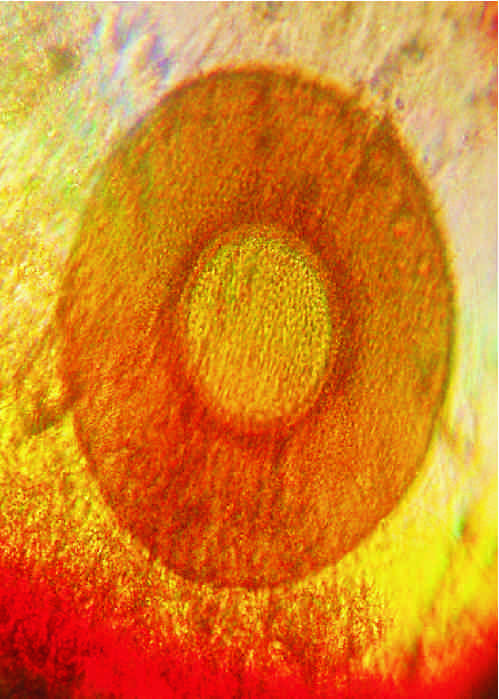

znalezione w odchodach - powiekszenie x120 i x500

(jest okragle, tylko na tych zdjeciach robi sie jajo)

Teraz o tym co (słabo

) widać. Na nr.1 to może być skorupka pełzaka - ameby. Na drugim - nie wiem (wydaje mi się zbyt symetryczny ten obiekt, żeby mógł być czymś, co nas może interesować

). Teoretycznie mógłby być niby jakąś cystą, niekoniecznie groźną, ale moim zdaniem jest zbyt symetryczny.

to sa fotki tego samego ustrojstwa w powiekszeniach x120 i x500,